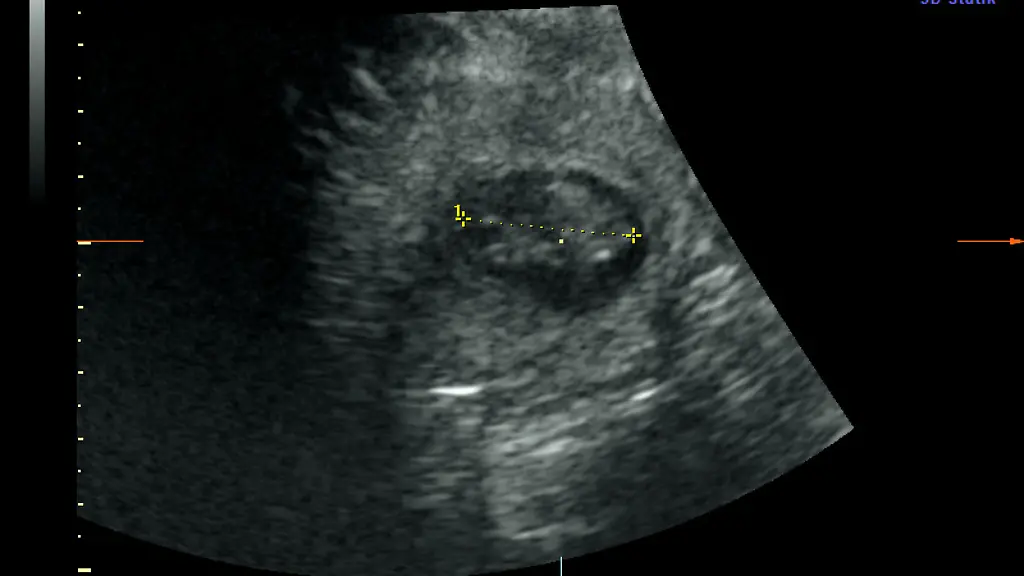

Ultraschall zeigt zwei JungtierePanda-Dame im Berliner Zoo ist erneut trächtig

Im Berliner Zoo wird wieder Panda-Nachwuchs erwartet. "Die Babys sind etwa 2,5 Zentimeter groß und müssen jetzt bis zur Geburt noch ordentlich wachsen", sagte Thomas Hildebrandt, Leiter der Abteilung für Reproduktionsmanagement am Leibniz-Institut für Zoo- und Wildtierforschung laut Pressemitteilung. Im Panda Garden sei am Sonntag ein kleiner Jubel ausgebrochen, teilte der Zoo mit.

Die Panda-Dame hatte sich zuletzt nicht besonders kooperativ gezeigt. "Trotz sichtlichen Bauchkneifens" habe Meng Meng sich aber überzeugen lassen, "in den aufrechten Stand zu kommen und das kühle Ultraschall-Gel sowie die Untersuchung mit der Ultraschall-Sonde zu akzeptieren", sagte der Veterinärmediziner, der als internationaler Experte bei der Reproduktion von Großen Pandas gilt. "Eine Untersuchung im Stehen hat schließlich die freudige Nachricht gebracht, dass Meng Meng mit zwei Jungtieren trächtig ist."